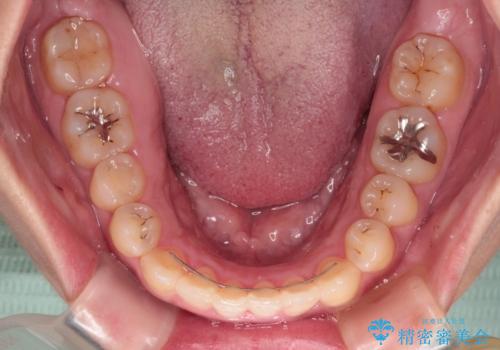

カリエールディスタライザーを併用したことで、すっきりとした口元になり、上下の正中を合わせることができました。